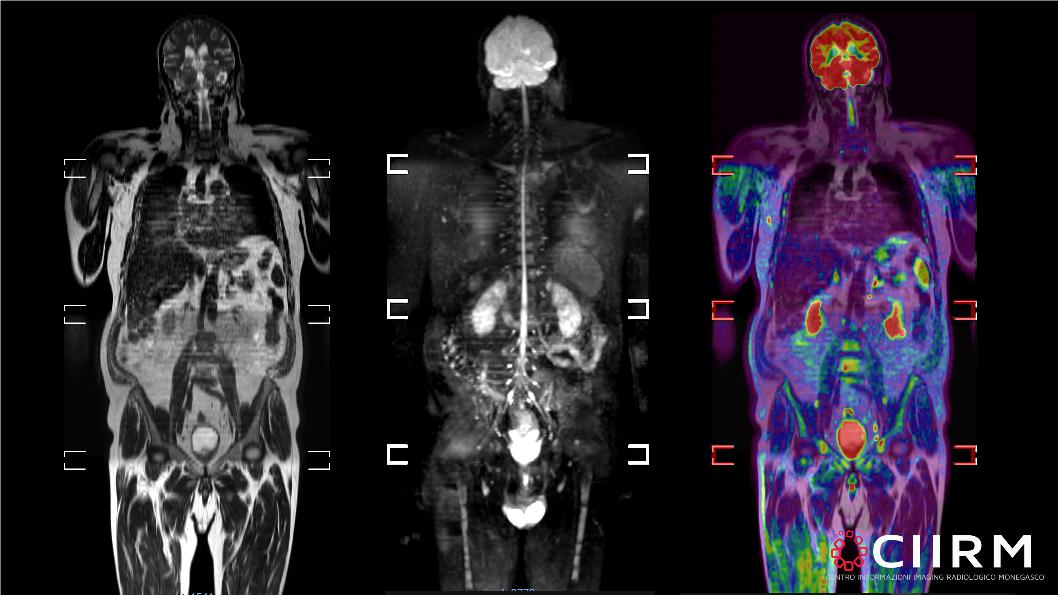

RM Total Body DWI Diffusione

La RM total body con tecnica di diffusione (definita anche WB-DWI Whole Body Diffusion Weighted Imaging) è una particolare tecnica di acquisizione che combina la sequenza di diffusione con l'unione delle immagini di più parti del corpo. La sua grande capacità è quella di poter fornire delle informazioni morfologiche (cioè sull'aspetto dei tessuti o degli organi) insieme ad informazioni funzionali (detto in modo grossolano sullo stato di salute delle cellule). Queste caratteristiche hanno fatto si che la tecnica prendesse piede nel campo dei controlli di pazienti affetti da tumore conosciuto o fortemente sospetto, in particolare nei linfomi, mieloma multiplo o metastasi diffuse.

Il risultato dell'esame è incredibilmente interpretabile anche dal pubblico in quanto vengono fornite una serie di immagini del corpo intero (dalla testa alle cosce) con vista frontale.

Come già detto le immagini acquisite sono di tipo morfologico (Sequenze T2 o T1) e di tipo funzionale (le sequenze di Diffusione)